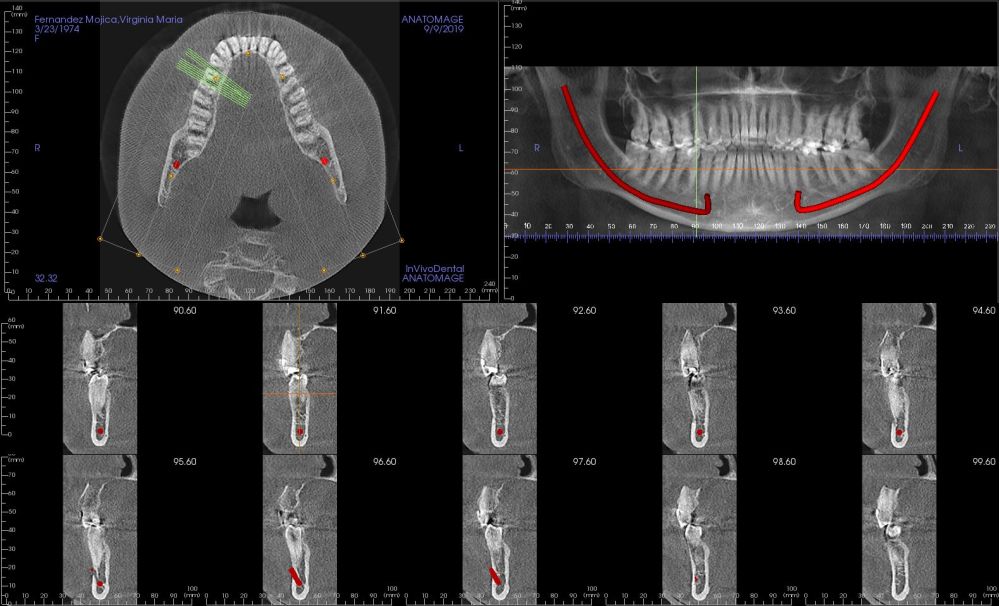

Presentamos el caso de una paciente de 47 años que acude al servicio de cirugía maxilofacial por dolor en el área sinusal derecha en Junio de 2020. Se realizó una radiografía panorámica en la que se observó una imagen sospechosa en la zona del primer cuadrante. Dichos hallazgos se confirmaron con la realización de una tomografía axial computarizada (TAC) facial y una resonancia magnética en las que se identifica una extensa lesión tumoral que ocupaba el seno maxilar derecho e infiltraba el suelo de la órbita derecha y fosa nasal derecha (Figuras 1, 2 y 3). Tras la realización de una biopsia, se confirmó la presencia de un carcinoma adenoide quístico. De este modo, se planificó la extirpación quirúrgica y la fijación mediante placas preformadas sobre un modelo impreso en poliamida (Figura 4).